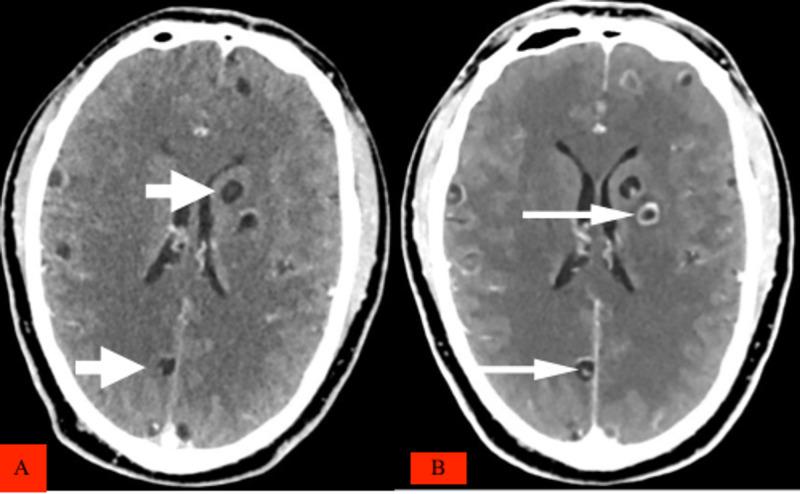

囊尾蚴在全身播散并累及心肺是一种非常罕见的情况,也是囊尾蚴病表现的一种不常见形式。我们报告一例罕见病例,患者为一名48岁来自坦桑尼亚城市的非洲男性,最初因冠状动脉计算机断层扫描血管造影(CCTA)被转诊至我们的放射科,但在对患者进一步评估时偶然发现其有反复抽搐、意识丧失、单次短暂视力丧失及近期皮肤结节的病史。对于诊断这种疾病而言,对成年起病癫痫患者进行全面临床和放射学评估的价值再怎么强调也不为过。播散性囊尾蚴病的管理很复杂,因此应根据个体情况进行调整,并关注临床表现。